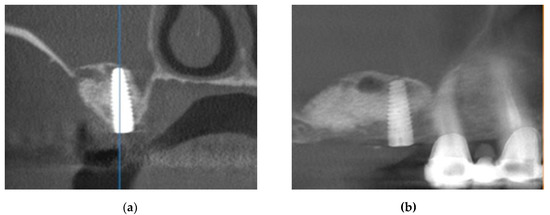

This case involved a 50-year-old male patient who presented to the clinic with a maxillary cantilever cemented prosthetic restoration. The patient affirmed that the functional role of this restoration became completely inadequate, with no possibility of mastication on the right side. The first step of the procedure included a clinical examination (Figure 1), where the missing maxillary right first and second molars were remarked. The first molar was extracted two years ago and the second molar over ten years ago. The intraoral examination showed a healthy gingival and mucosal status. For an accurate diagnosis, a radiological evaluation was performed. The treatment options were explained, and the patient was also informed about the benefits and risks of each treatment option. As he wanted to avoid a removable prosthesis due to its inconvenience, the chosen treatment option was an implant-supported crown restoration.

Figure 1. (a) Initial clinical assessment; (b) preoperative orthopantomogram (OPG) showing an insufficient height for implant insertion in the maxillary right first molar edentulous site.